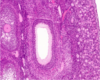

מהם המאפיינים ההיסטולוגיים של שחלות?

ovary

שחלה עטופה באפיתל גרמינלי חד שכבתי קובייתי

תחתיו של טוניקה אלבוגינאה- שכבה ורודה דקה של רקמת חיבור צפופה

סטרומה מאוד צלולרית- המון תאים. אופייני לשחלה

מה המאפיינים של הקורטקס והמדולה בשחלה?

קורטקס- זקיקים של השחלה, ביציות בשלבי התבגרות שונים

מדולה- שכבת חיבור רפה וכלי דם

אין בין שניהם גבול ברור.